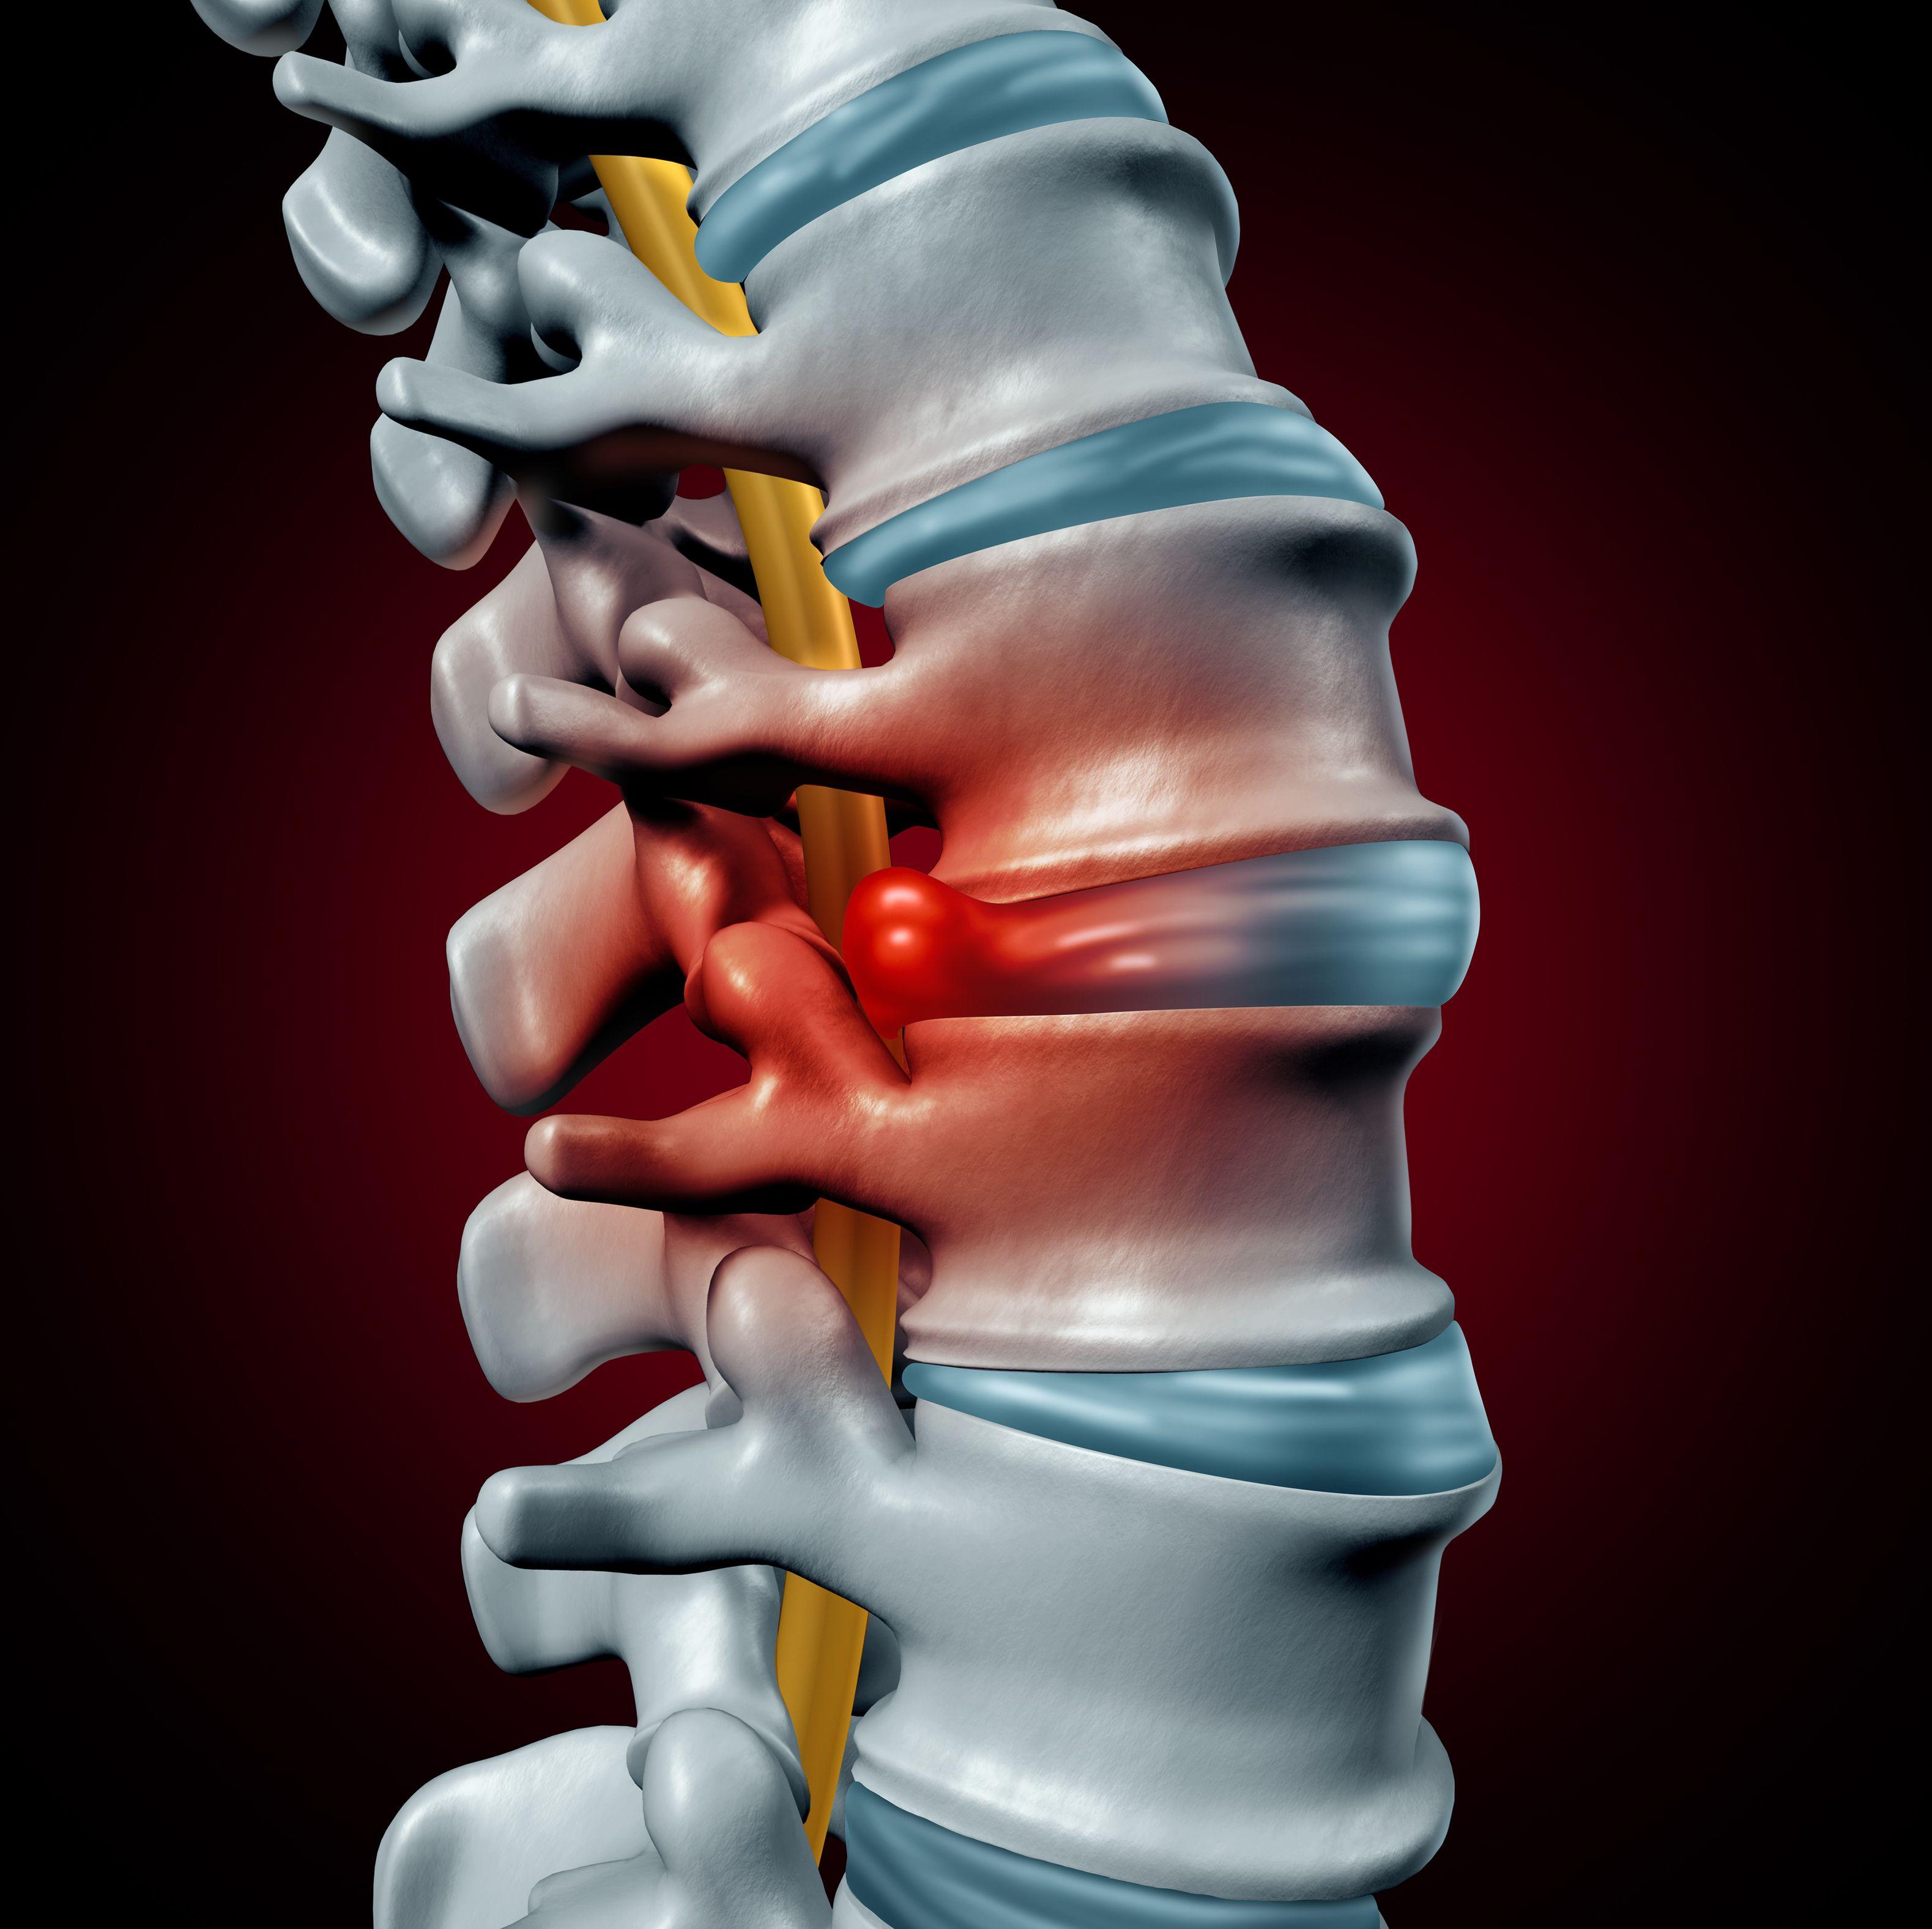

Comprehensive Guide to Torn Discs: Causes, Symptoms, and Treatments

The Deuk Spine blog is dedicated to providing education and information on the root cause causes of back and neck pain, treatment solutions, industry insights, and the alternatives to spinal fusion surgery including our proprietary Deuk Laser Disc Repair.